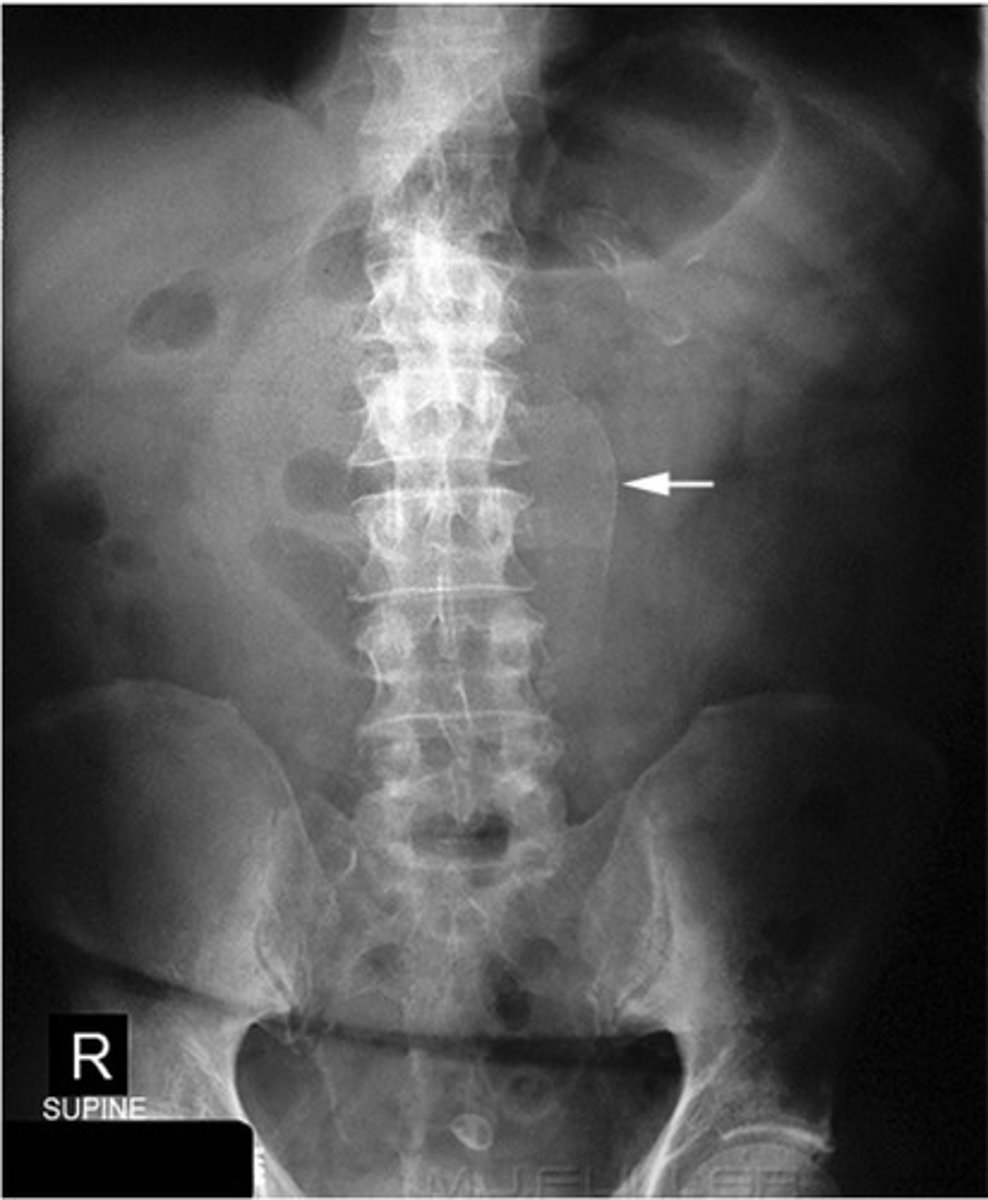

Abdominal aortic aneurysm calcification (pic 2)

Abdominal aortic aneurysm calcification (pic 3)